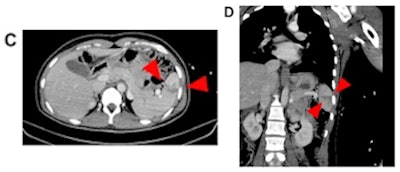

Case 2: After reporting a blunt trauma to the abdomen by her partner, abdominal CT of a 41-year-old female revealed splenic injury with parenchymal laceration (arrowheads) without intra-abdominal bleeding (C, D). The injury was treated conservatively and regularly checked by ultrasound. The bleeding stopped spontaneously. Police were informed.